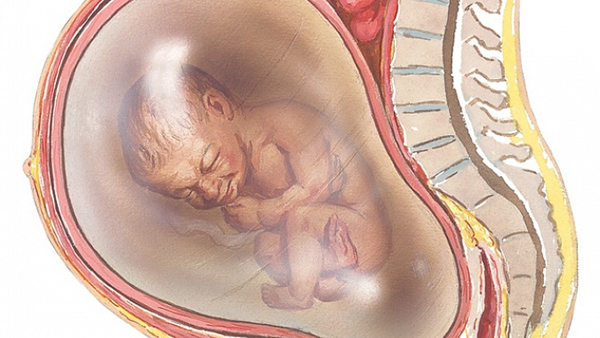

Thực ra nước ối là khám niệm ám chỉ chất dịch loãng màu vàng nhạt bao quanh cơ thể thai nhi, tạo không gian phát triển tự do cho bé, giúp bé duy trì thân nhiệt và nó chỉ xuất hiện trong tuần 12. Nước ối được coi như là một lớp đệm giúp bé tránh va đập, tổn thương, thúc đẩy sự phát triển của xương và cơ bắp. Chỉ số nước ối tính theo mm trong từng giai đoạn thai kì sẽ khác nhau, mẹ sẽ gặp nguy hiểm nếu bị thiếu hoặc đa ối.

Để biết tình trạng của cơ thể mình ra sao, bạn cần nắm được chỉ số nước ối tiêu chuẩn hay còn gọi là chỉ số AFI. Ví dụ như ở tuần thứ 20 lượng nước ối là 350ml, từ 25 đến 26 tuần tuổi thì là 670ml. từ 32 đến 36 tuần tuổi thì là 800ml. Tuy nhiên vào tuần từ 40 đến 42 thì lượng nước ối sẽ giảm xuống chỉ còn từ 540 đến 600ml.

Để đo được chính xác chỉ số nước ối thì bác sĩ sẽ chia buồng tử cung ra thành 4 phần, 2 đường sẽ cắt nhau tại rốn của bạn, Bác sĩ sẽ đo chiều dài của túi ối sâu nhất mỗi phần. Tổng số nước ối của cả 4 phần chính là chỉ số nước ối của thai phụ.